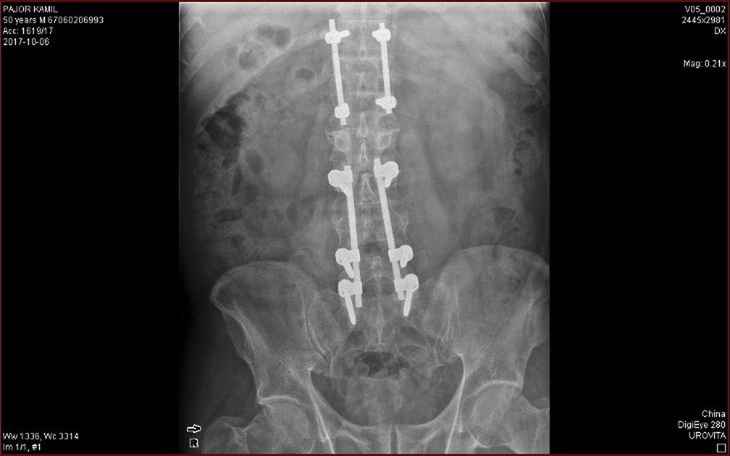

Zbiórka jest organizowana dla osoby która wielokrotnie uratowała innym życie , jest wieloletnim Zasłużonym Honorowym Dawca Krwi organizatorem zbiórek krwi i pomocy dla innych . Teraz po wielu latach ciężkiej walki ze złamanym kręgosłupem osoba ta sama potrzebuje pomocy .